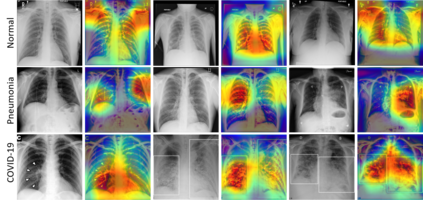

Recently, the outbreak of the novel Coronavirus disease 2019 (COVID-19) pandemic has seriously endangered human health and life. Due to limited availability of test kits, the need for auxiliary diagnostic approach has increased. Recent research has shown radiography of COVID-19 patient, such as CT and X-ray, contains salient information about the COVID-19 virus and could be used as an alternative diagnosis method. Chest X-ray (CXR) due to its faster imaging time, wide availability, low cost and portability gains much attention and becomes very promising. Computational methods with high accuracy and robustness are required for rapid triaging of patients and aiding radiologist in the interpretation of the collected data. In this study, we design a novel multi-feature convolutional neural network (CNN) architecture for multi-class improved classification of COVID-19 from CXR images. CXR images are enhanced using a local phase-based image enhancement method. The enhanced images, together with the original CXR data, are used as an input to our proposed CNN architecture. Using ablation studies, we show the effectiveness of the enhanced images in improving the diagnostic accuracy. We provide quantitative evaluation on two datasets and qualitative results for visual inspection. Quantitative evaluation is performed on data consisting of 8,851 normal (healthy), 6,045 pneumonia, and 3,323 Covid-19 CXR scans. In Dataset-1, our model achieves 95.57\% average accuracy for a three classes classification, 99\% precision, recall, and F1-scores for COVID-19 cases. For Dataset-2, we have obtained 94.44\% average accuracy, and 95\% precision, recall, and F1-scores for detection of COVID-19. Our proposed multi-feature guided CNN achieves improved results compared to single-feature CNN proving the importance of the local phase-based CXR image enhancement (https://github.com/endiqq/Fus-CNNs_COVID-19).